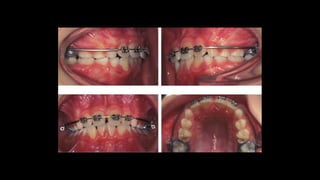

Casos clínicos

4x2